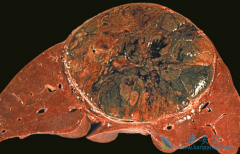

肝癌患者服用 乐伐替尼 (Lenvima)多长时间见效?有很多肝癌患者服用乐伐替尼一周左右,疼痛明显缓解,下肢浮肿改善,一个月后复查,肿瘤明显缩小。目前乐伐替尼原研药只在日本、欧美国家上市,价格非常昂贵,不过日本卫材的乐伐替尼在印度的销售价格仍然 ...